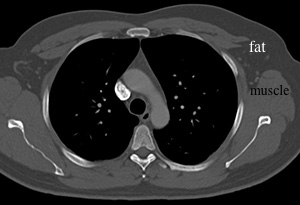

LUNG window-this shows all of the tiny bronchi and vessels in the lungs, as well as pleural lining, but is not good for looking at other types of tissue, like the chest wall (again, fat and muscle are similar shades of gray)